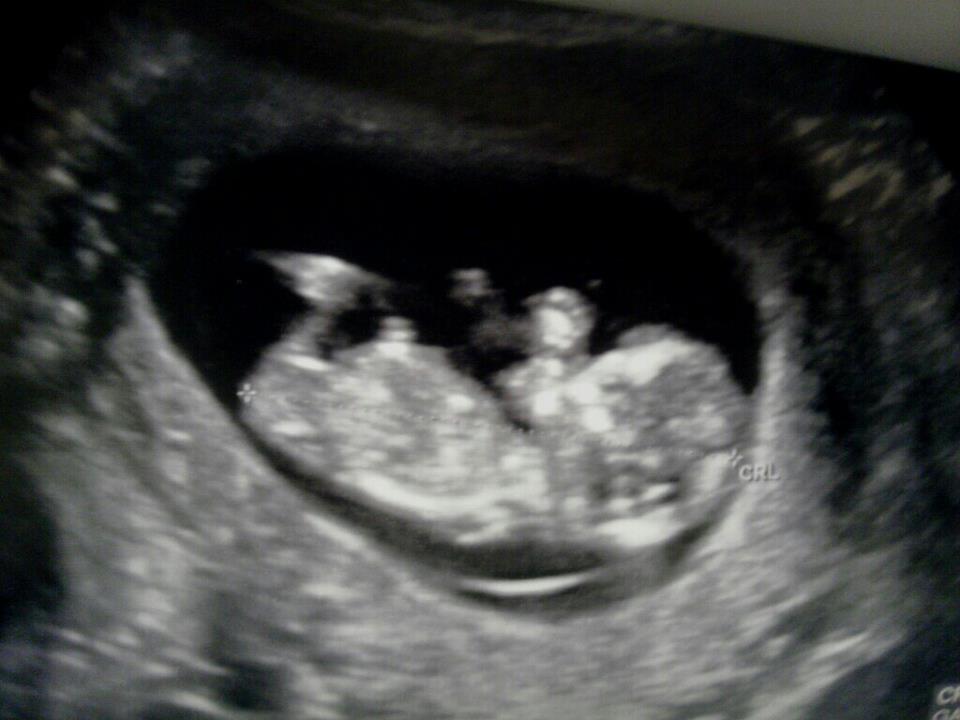

Thats soo tricky!! I'm not sure if the bottom pic shows a little detatched bobble or is it attached??? My lean is girl as it just looks really long and bright, keep us posted on this one won't you!!

There was a shot between the legs...I know it's way too early for a potty shot but it was a bright white circle-ish spot. Definitely obvious. My doctor saw those pictures and I told him I was thinking girl based on the old wives tale of a high heartrate etc, and he gave me the side eye like I was wrong but he didn't want to say yet.

I don't see a nub.